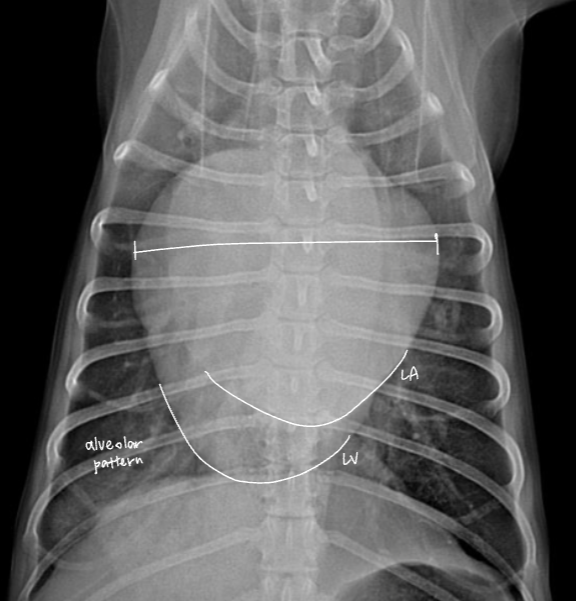

| CHF (Congestive Heart Failure, ์ธํ์ฑ ์ฌ๋ถ์ ) |

| 1) LCHF |

| Radiographic signs - Pulmonary edema - PV enlargement - (cats) pleural effusion, patch alveolar pattern - LA enlargement (backpack sign, double wall sign) - alveolar pattern |

![]() ![]() |